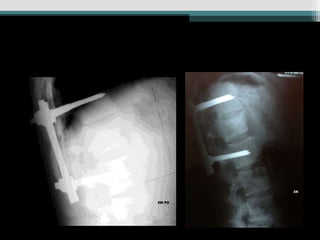

Caso 1 (34 anos, queda, Fk e)

Caso 2 (25 anos, auto, Fk a)

Caso 3 (24 anos, queda Fk e)

Caso 4 (19 anos, auto, Fk e)

Caso 1 (34anos, queda, Fk e)

Caso 2 (25anos, auto, Fk a) www.traumatologiaeortopedia.com.b

Caso 3 (24anos, queda Fk e)

Caso 4 (19anos, auto, Fk e)